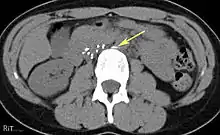

Of these IVC filter side effects, 328 involved device migration, 146 involved embolizations after detachment of device components, 70 involved perforation of the IVC, and 56 involved filter fracture. Much of the medical community believes that this large number of adverse events is related to the heart filter remaining in place for longer than necessary.

- 9% (12 of 132 patients) delayed filter penetration of the IVC greater than 3 mm

- Parts of filter broke off in 2% (5 of 230 patients)

- Caval filter migrated to heart or pulmonary artery (4 patients)

- Filter fracture: Broken struts migrate to retroperitoneum, requiring exploration.[20] Also struts can migrate to the heart and can cause pericardial effusion and tamponade.[21]